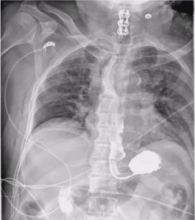

Technique: The patient was a 68-year-old gentleman with Parkinson's disease who had difficulty swallowing. A barium esophagogram and CT scan of the chest revealed a 4 cm epiphrenic esophageal diverticulum. Pre-operative EGD revealed the diverticulum arising at 32 cm from the incisors and the GE junction at 40 cm. The diverticulum, which contained retained food and tablets, was evacuated. Pulmonary function tests were adequate to perform a trans-thoracic operation. After intubation with a double lumen entrotracheal tube for lung isolation, EGD was performed on the table to empty the diverticulum of all its contents. An NGT was guided into the stomach. The patient was then repositioned in the left lateral decubitus position, prepped, and draped. The port placement is shown in the video. The diverticulum was mobilized and excised with a stapler, and the dehisced muscle was approximated. The esophageal hiatus was then dissected and the fat pad over the GE junction excised. The myotomy was performed and extended onto the stomach for 2 cm. A leak test was performed. The diaphragmatic hiatus was then approximated and the mediastinal pleura closed. Marcaine multilevel intercostal nerve block was performed. Blake drains were positioned in the chest.